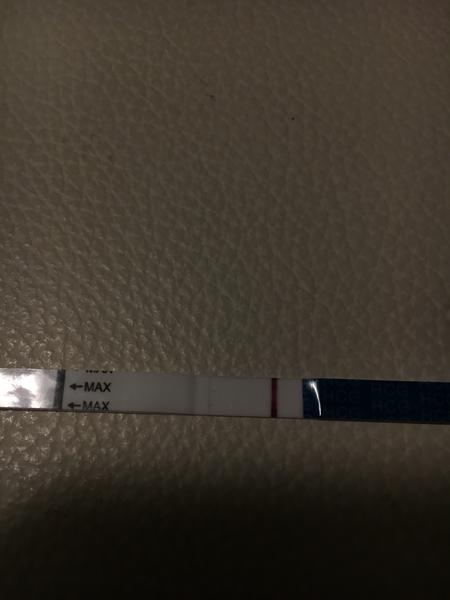

Těhotenský test. Dávám fotku. Co myslíte?

dnes jsem si dělala testík...

Udělal jsem radši ještě jeden - jmenuje se ForYou... Tam se objevil slabý duch, ale až tak za 3minuty! Šla jsem ven se psi a když jsem se vrátila, tak duch byl silnější...no ale to bylo skoro po půl hodině!

Tak nevim ... ☹ Dávám fotku, skuste posoudit...

@flylight tak já ho zkoušela taky, mám ho i tady v zásobě. Některé testy mají menší barvivo, takže můžou ukázat čárku později, než jiné. S tímto testem nemám zkušenost, že by dělal falešné čárky. A když se objevila, tak je to jasné 🙂 Někomu se hold i ty čárky ukáží po vynechání MS, taky se říká, že to je nejjistější pro testování.

Já tam čárku vidím 🙂 v té době jsem měla taky jen nepatrnou druhou čárku 🙂